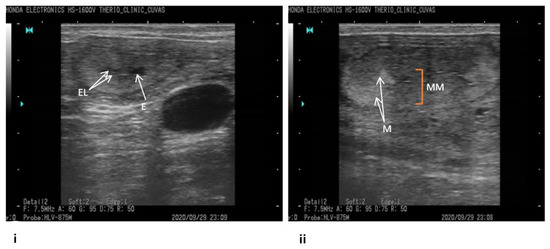

2.1. Tracking Bovine Endometritis

- Fissore, R.A.; Edmondson, A.J.; Pashen, R.L.; Bondurant, R.H. The use of ultrasonography for the study of the bovine reproductive tract. II. Non-pregnant, pregnant and pathological conditions of the uterus. Anim. Reprod. Sci. 1986, 12, 167–177. [Google Scholar] [CrossRef]

- Pierson, R.A.; Ginther, O.J. Ultrasonic imaging of the ovaries and uterus in cattle. Theriogenology 1988, 29, 21–37. [Google Scholar] [CrossRef]

- Ihnatsenka, B.; Boezaart, A.P. Ultrasound: Basic understanding and learning the language. Int. J. Shoulder Surg. 2010, 4, 55. [Google Scholar]